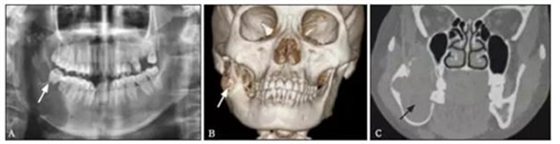

全景片、錐形束CT(cone beam computedtomography,CBCT)及螺旋CT結(jié)果提示:右側(cè)下頜骨體C6至下頜升支乙狀切跡區(qū)域可見一囊性病損,與正常骨邊界清楚,中心密度均勻,內(nèi)可見大小不等的分隔,邊緣呈切跡狀改變,病變累及乙狀切跡和喙突,向頰舌側(cè)膨隆明顯,舌側(cè)骨密質(zhì)不連續(xù),頰側(cè)骨密質(zhì)外可見骨膜反應(yīng),C78牙根有吸收。右下頜骨頰舌側(cè)不連續(xù)(圖1)。

圖1 患者術(shù)前檢查

A:全景片(箭頭所指為牙齒截根樣吸收);

B:螺旋CT平掃(箭頭所指為病變突破骨組織);

C:CBCT(箭頭所指為病變位置)。